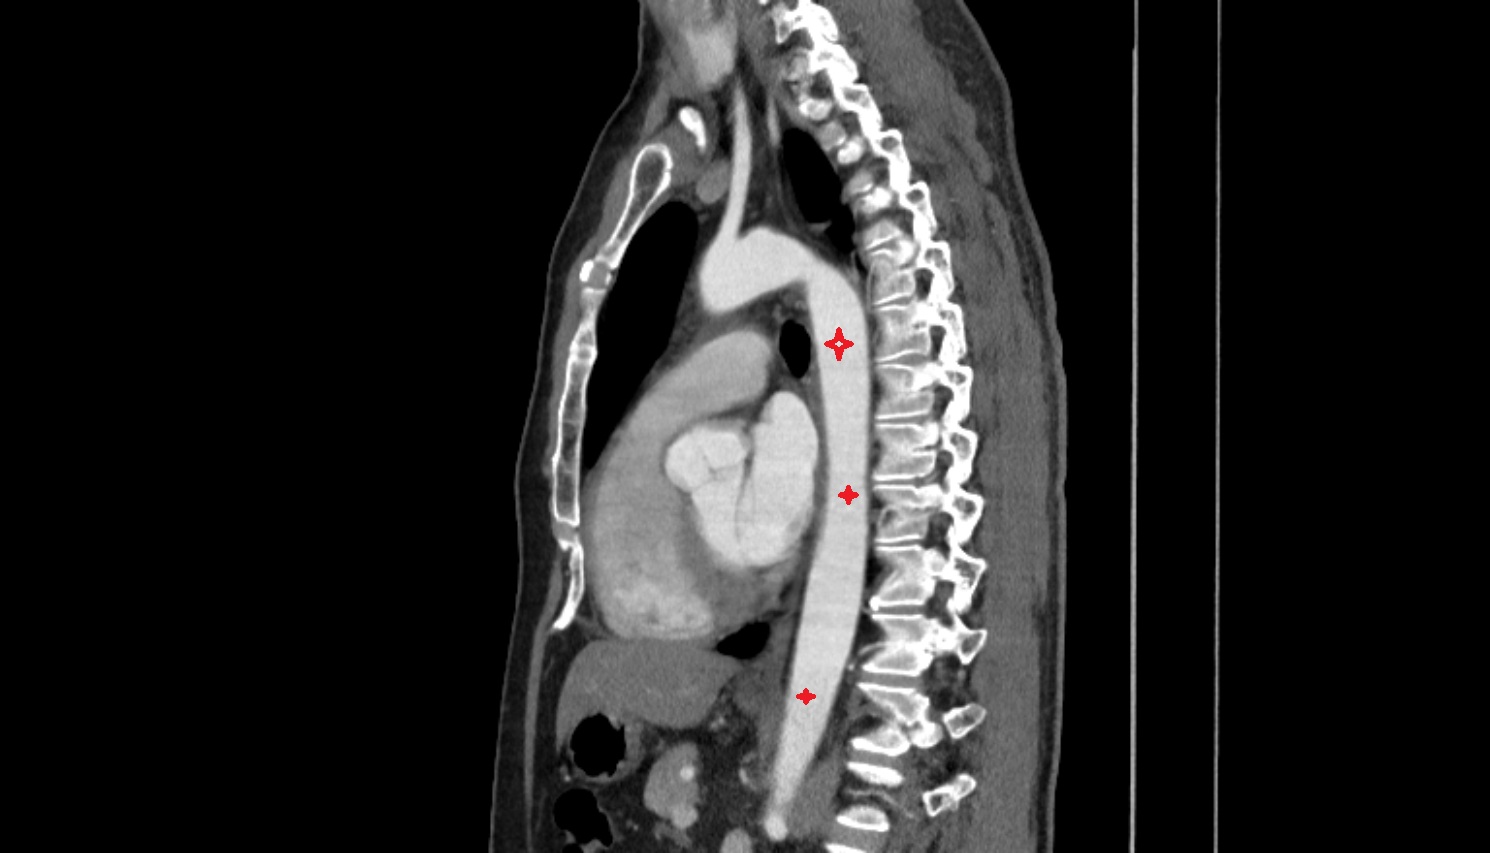

- Thoracic part of esophagus

- Ascending aorta

- Arch of aorta

- Descending thoracic aorta

- Esophagus